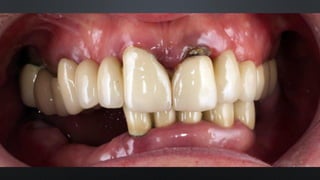

• OCLUSÃO FISIOLÓGICA, DETERMINADA PELA POSIÇÃO DO CÔNDILO

RELAÇÃO ENTRE ARCOS

RELAÇÃO CÊNTRICA (RC)

• O CÔNDILO E O DISCO SE ENCONTRAM EM UMA POSIÇÃO MAIS SUPERIOR E

ANTERIOR NA FOSSA ARTICULAR

• POSIÇÃO DE REABILITAÇÃO EM PACIENTES DESDENTADOS OU COM OCLUSÃO

INSTÁVEL

• TODO PACIENTE PODE SER LEVADA À RC